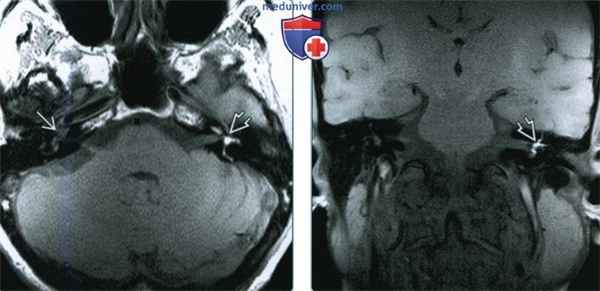

(Слева) При аксиальной МРТ Т1 ВИ без контраста на уровне внутренних слуховых каналов определяется гиперинтенсивный сигнал в перепончатом лабиринте внутреннего уха слева, обусловленный интралабиринтным кровоизлиянием (ИЛК). Сравните его с нормальным жидкостным сигналом справа.

(Справа) При корональной МРТ Т1 ВИ FS у этого же пациента определяется, что гиперинтенсивный сигнал во внутреннем ухе слева не обусловлен жиром, поскольку он сохраняется несмотря на подавление сигнала от жира. Изменения исключают интралабиринтную шванному и подтверждают диагноз ИЛК.